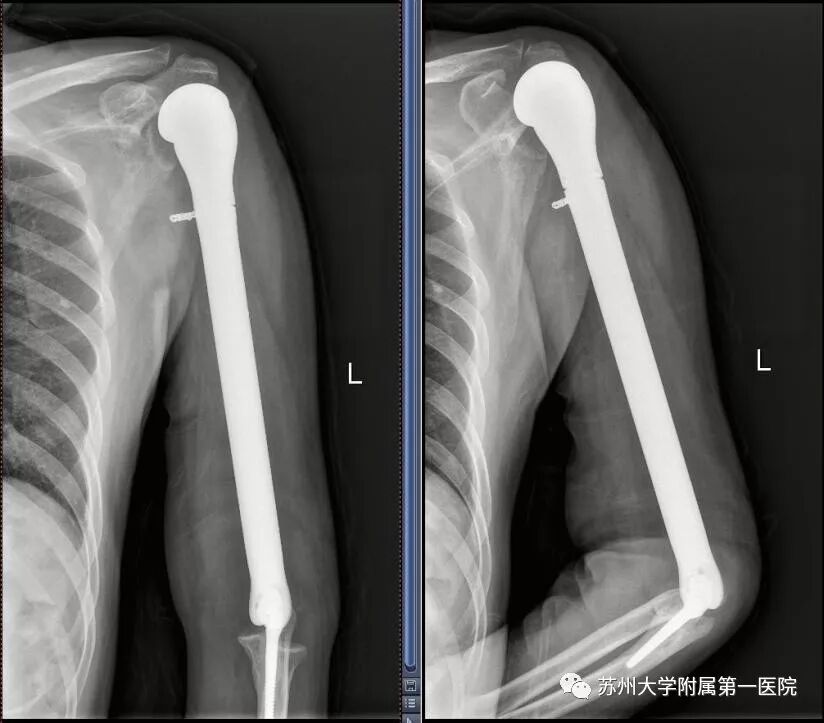

方大叔第一次手术后复发的X线片

陆俭主任仔细查看方大叔的病情后发现,由于方大叔花费了很长时间四处寻医,一定程度上耽误了就医时间,如果再拖延下去,过不了多久,肿瘤就会转移别的部位!若是转移到尺桡骨,就只能选择截肢了,更进一步就是全身多发转移而死亡,开展治疗刻不容缓!